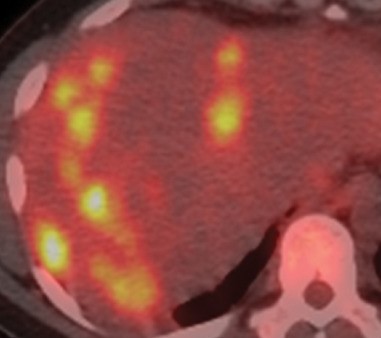

Presence of multiple metastases in the right lobe of the liver, 3 years after left hemicolectomy (Courtesy Dr. V. Penopoulos)